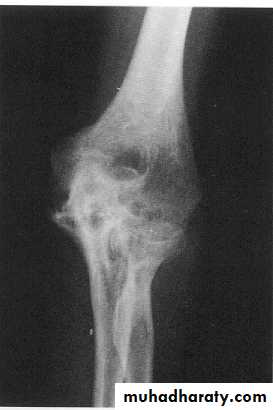

HAEMOPHILIA - HAEMARTHROSIS

CHRONIC JOINT BLEEDING

Long-term effects of Joint bleeds?

Repeated bleeding causes synovium (lining) to swell

The synovium stops producing the slippery, oily fluid that helps the joint move.

Damages the cartilage- joint stiff, painful and unstable.With time, most of the cartilage breaks down and some bone wears away. The whole process is called haemophilic arthropathy.